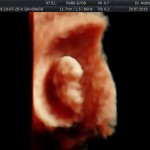

- La edad gestacional (calculo preciso del tiempo de embarazo)

- La vitalidad embrionaria (latido cardiaco)